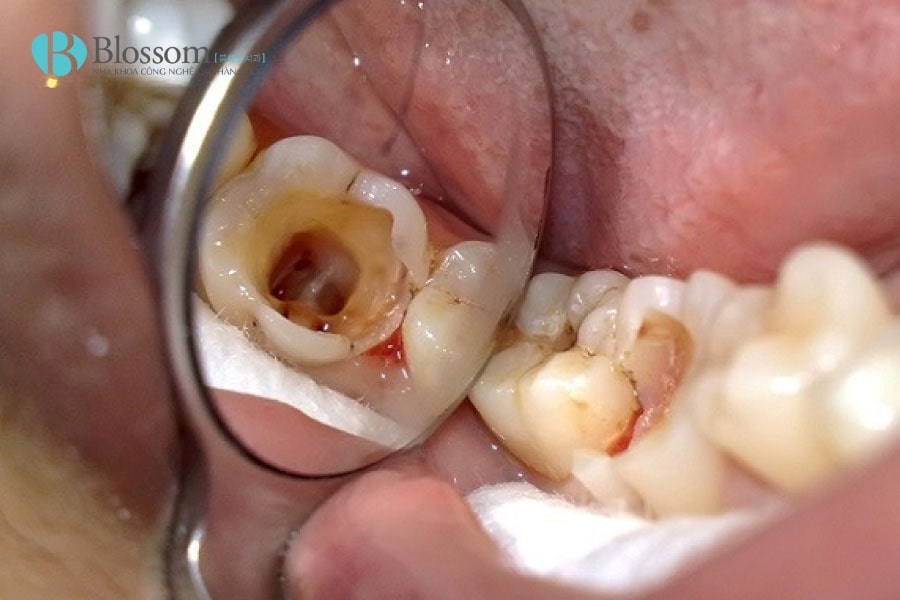

Cách làm chết tủy răng tại nhà không thể làm chết tủy răng một cách an toàn, triệt để

Cách làm chết tủy răng tại nhà tiềm ẩn nhiều nguy hiểm